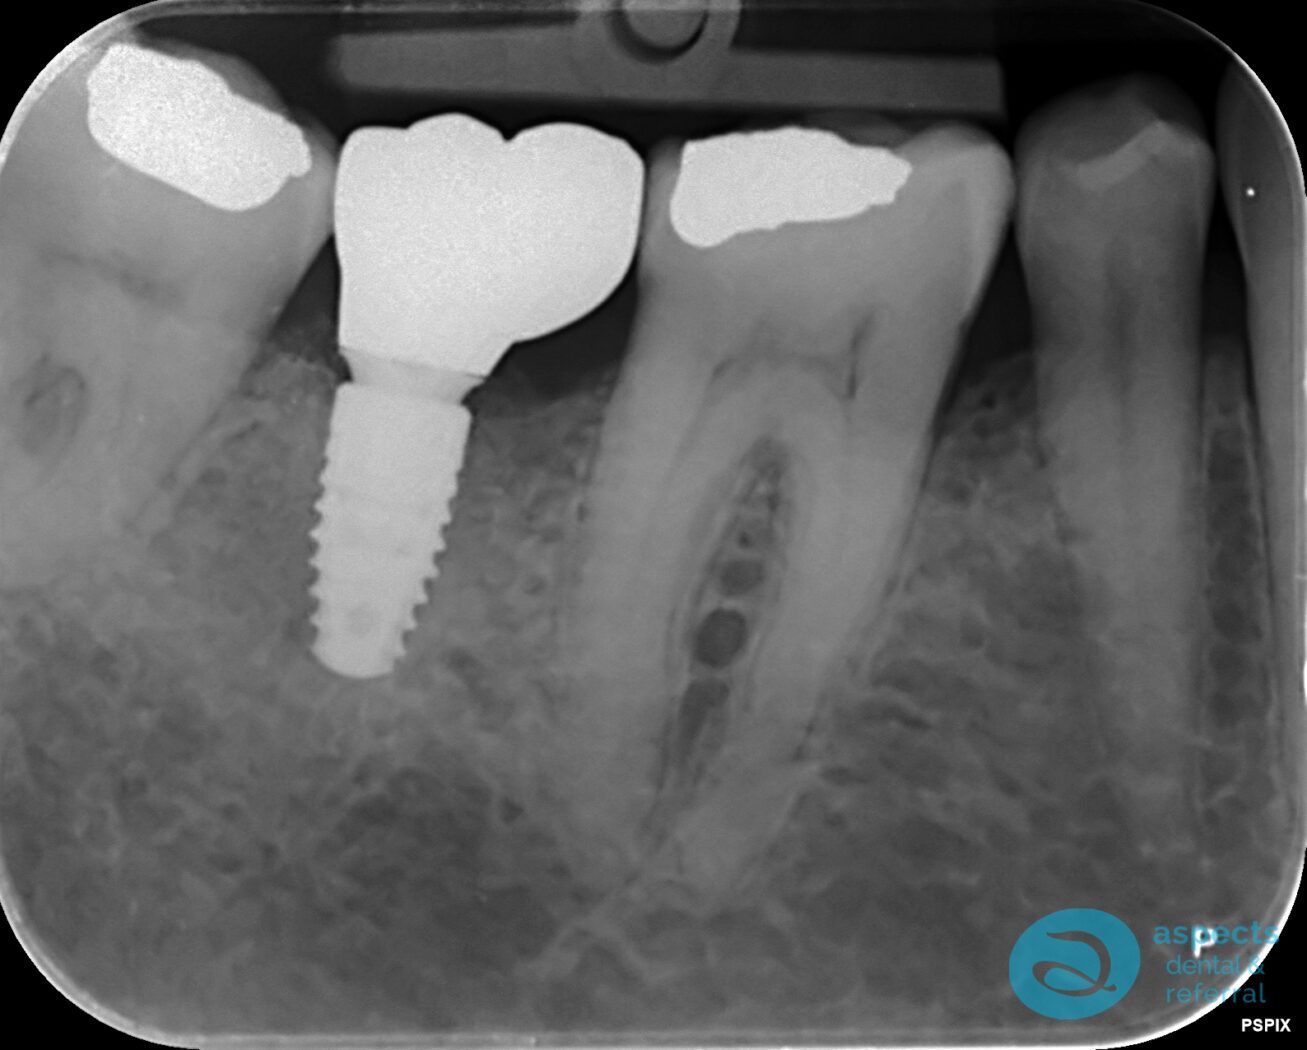

After a healing period of 12 weeks, a Dental Implant was successfully placed at the extraction site. Following appropriate osseointegration and healing, the implant was restored with an all-ceramic zirconia crown, providing both functional and aesthetic rehabilitation.

After Dental Implant Xray